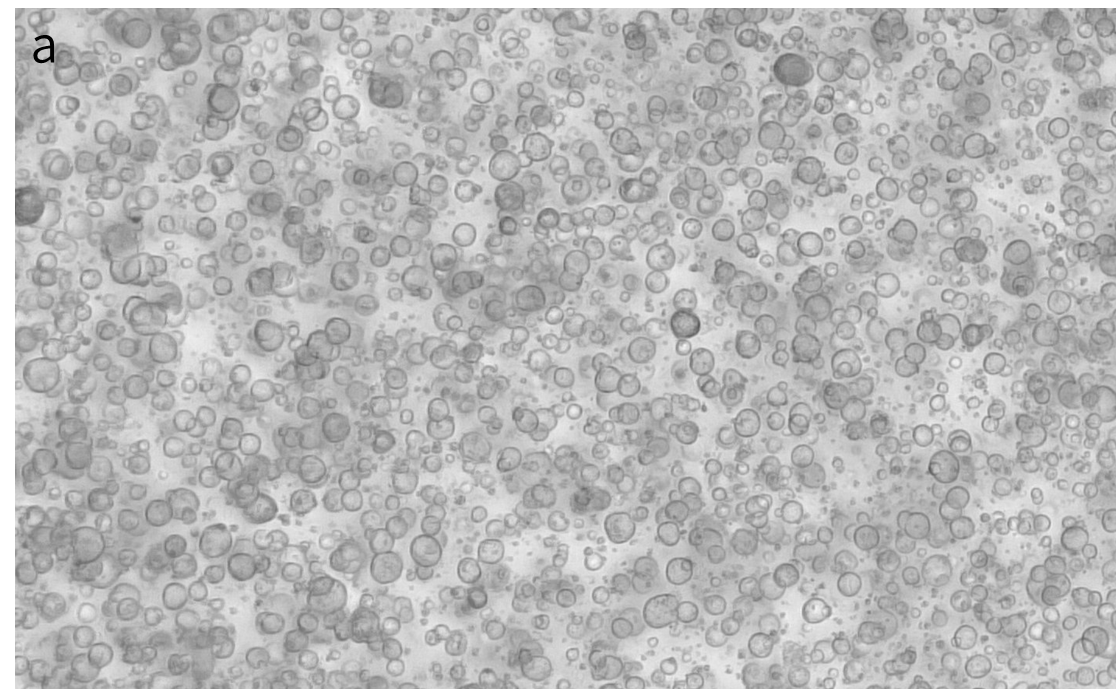

a.乳腺癌类器官明场

此培养基可以用于人乳腺癌类器官的建立与维持。

乳腺癌类器官培养试剂盒,为类器官的复苏 、 培养及冻存提供了经过优化的、高效并稳定的整体解决方案 ,同时保持肿瘤的异质性。

使用乳腺癌类器官培养试剂盒建立的类器官,可用于多种应用场景,包括肿瘤疾病建模、药效评估,毒性评价等。